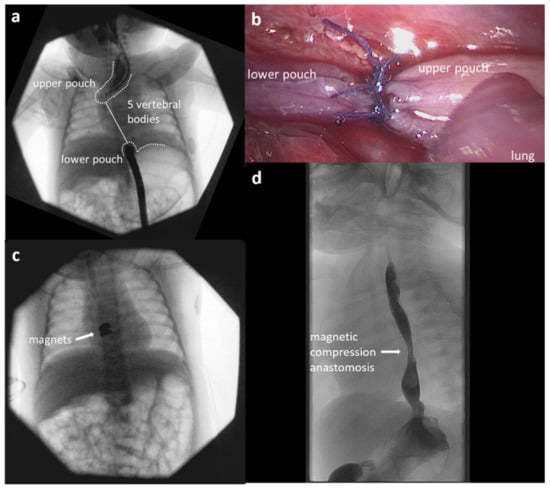

3.3. Case Report